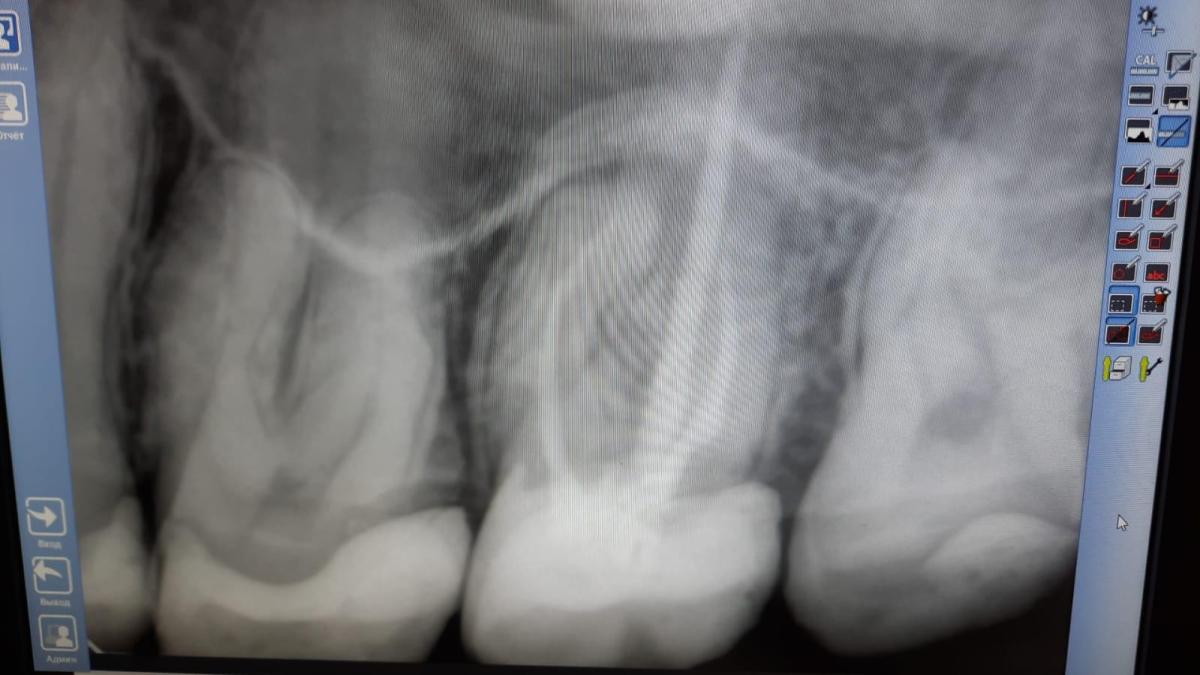

Откололся кусок зуба. Зуб с массивной пломбой и штифтом.

Врач советует удалить зуб и поставить имплант. Можно ли сохранить зуб и установить коронку?

а нет ли воспаления корня рядом со штифтом?

Зуб надо перелечить!